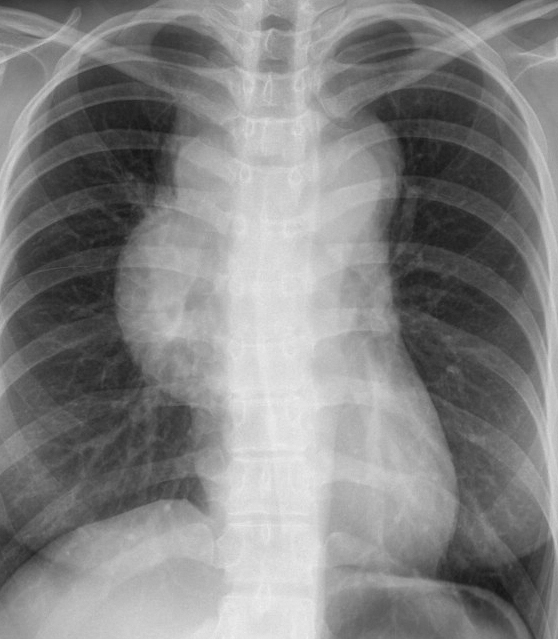

Gallery Mediastinum Lymphoma 7a

7a